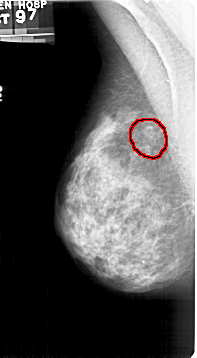

A_1427_1.LEFT_MLO

LEFT_MLO LINES 5356 PIXELS_PER_LINE 2941 BITS_PER_PIXEL 12 RESOLUTION 43.5 OVERLAY

FILE: A_1427_1.LEFT_MLO.OVERLAY

TOTAL_ABNORMALITIES 1

ABNORMALITY 1

LESION_TYPE CALCIFICATION TYPE AMORPHOUS DISTRIBUTION CLUSTERED

ASSESSMENT 4

SUBTLETY 3

PATHOLOGY BENIGN

TOTAL_OUTLINES 1

BOUNDARY